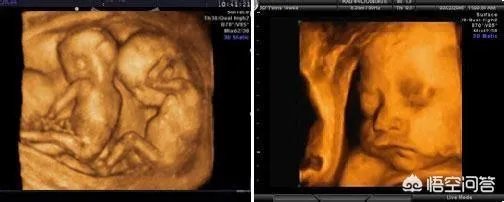

我们说双胞胎宝宝出生后之后会关系亲密,也会打架。那那么是胎宝宝的时候呢,在妈妈肚子里会不会打架呢?题主在做B超检查时候,就拍到了这样的画画,看着萌萌的。

之前网上面曾经看到过这样的一组动图,是双胞胎妈妈的B超影像。只见两个宝宝在一起,其中一个宝宝很是活跃,对着另外一个宝宝,一会动一下手,一会动一下脚的。从外面看起来就像是两个宝宝在打架一样。

那么实际上两个宝宝会打架吗?

就像是大家想的那样,两个宝宝如果是同卵双胞胎的话,他们是共用一个胎盘,并且在同一个羊膜腔内,两个宝宝是不可避免就会出现碰撞的,而且更容易出现的是,一个宝宝的活动把另外一个宝宝造成脐带绕颈了。

如果是异卵双胞胎的话,两个宝宝各有一个胎盘,相对而言离得就远了一些,相互的碰撞不会太多,但这也是相对而言。两个宝宝也是会在胎动过程中不断发生磕碰,看上去就像是打架一样。